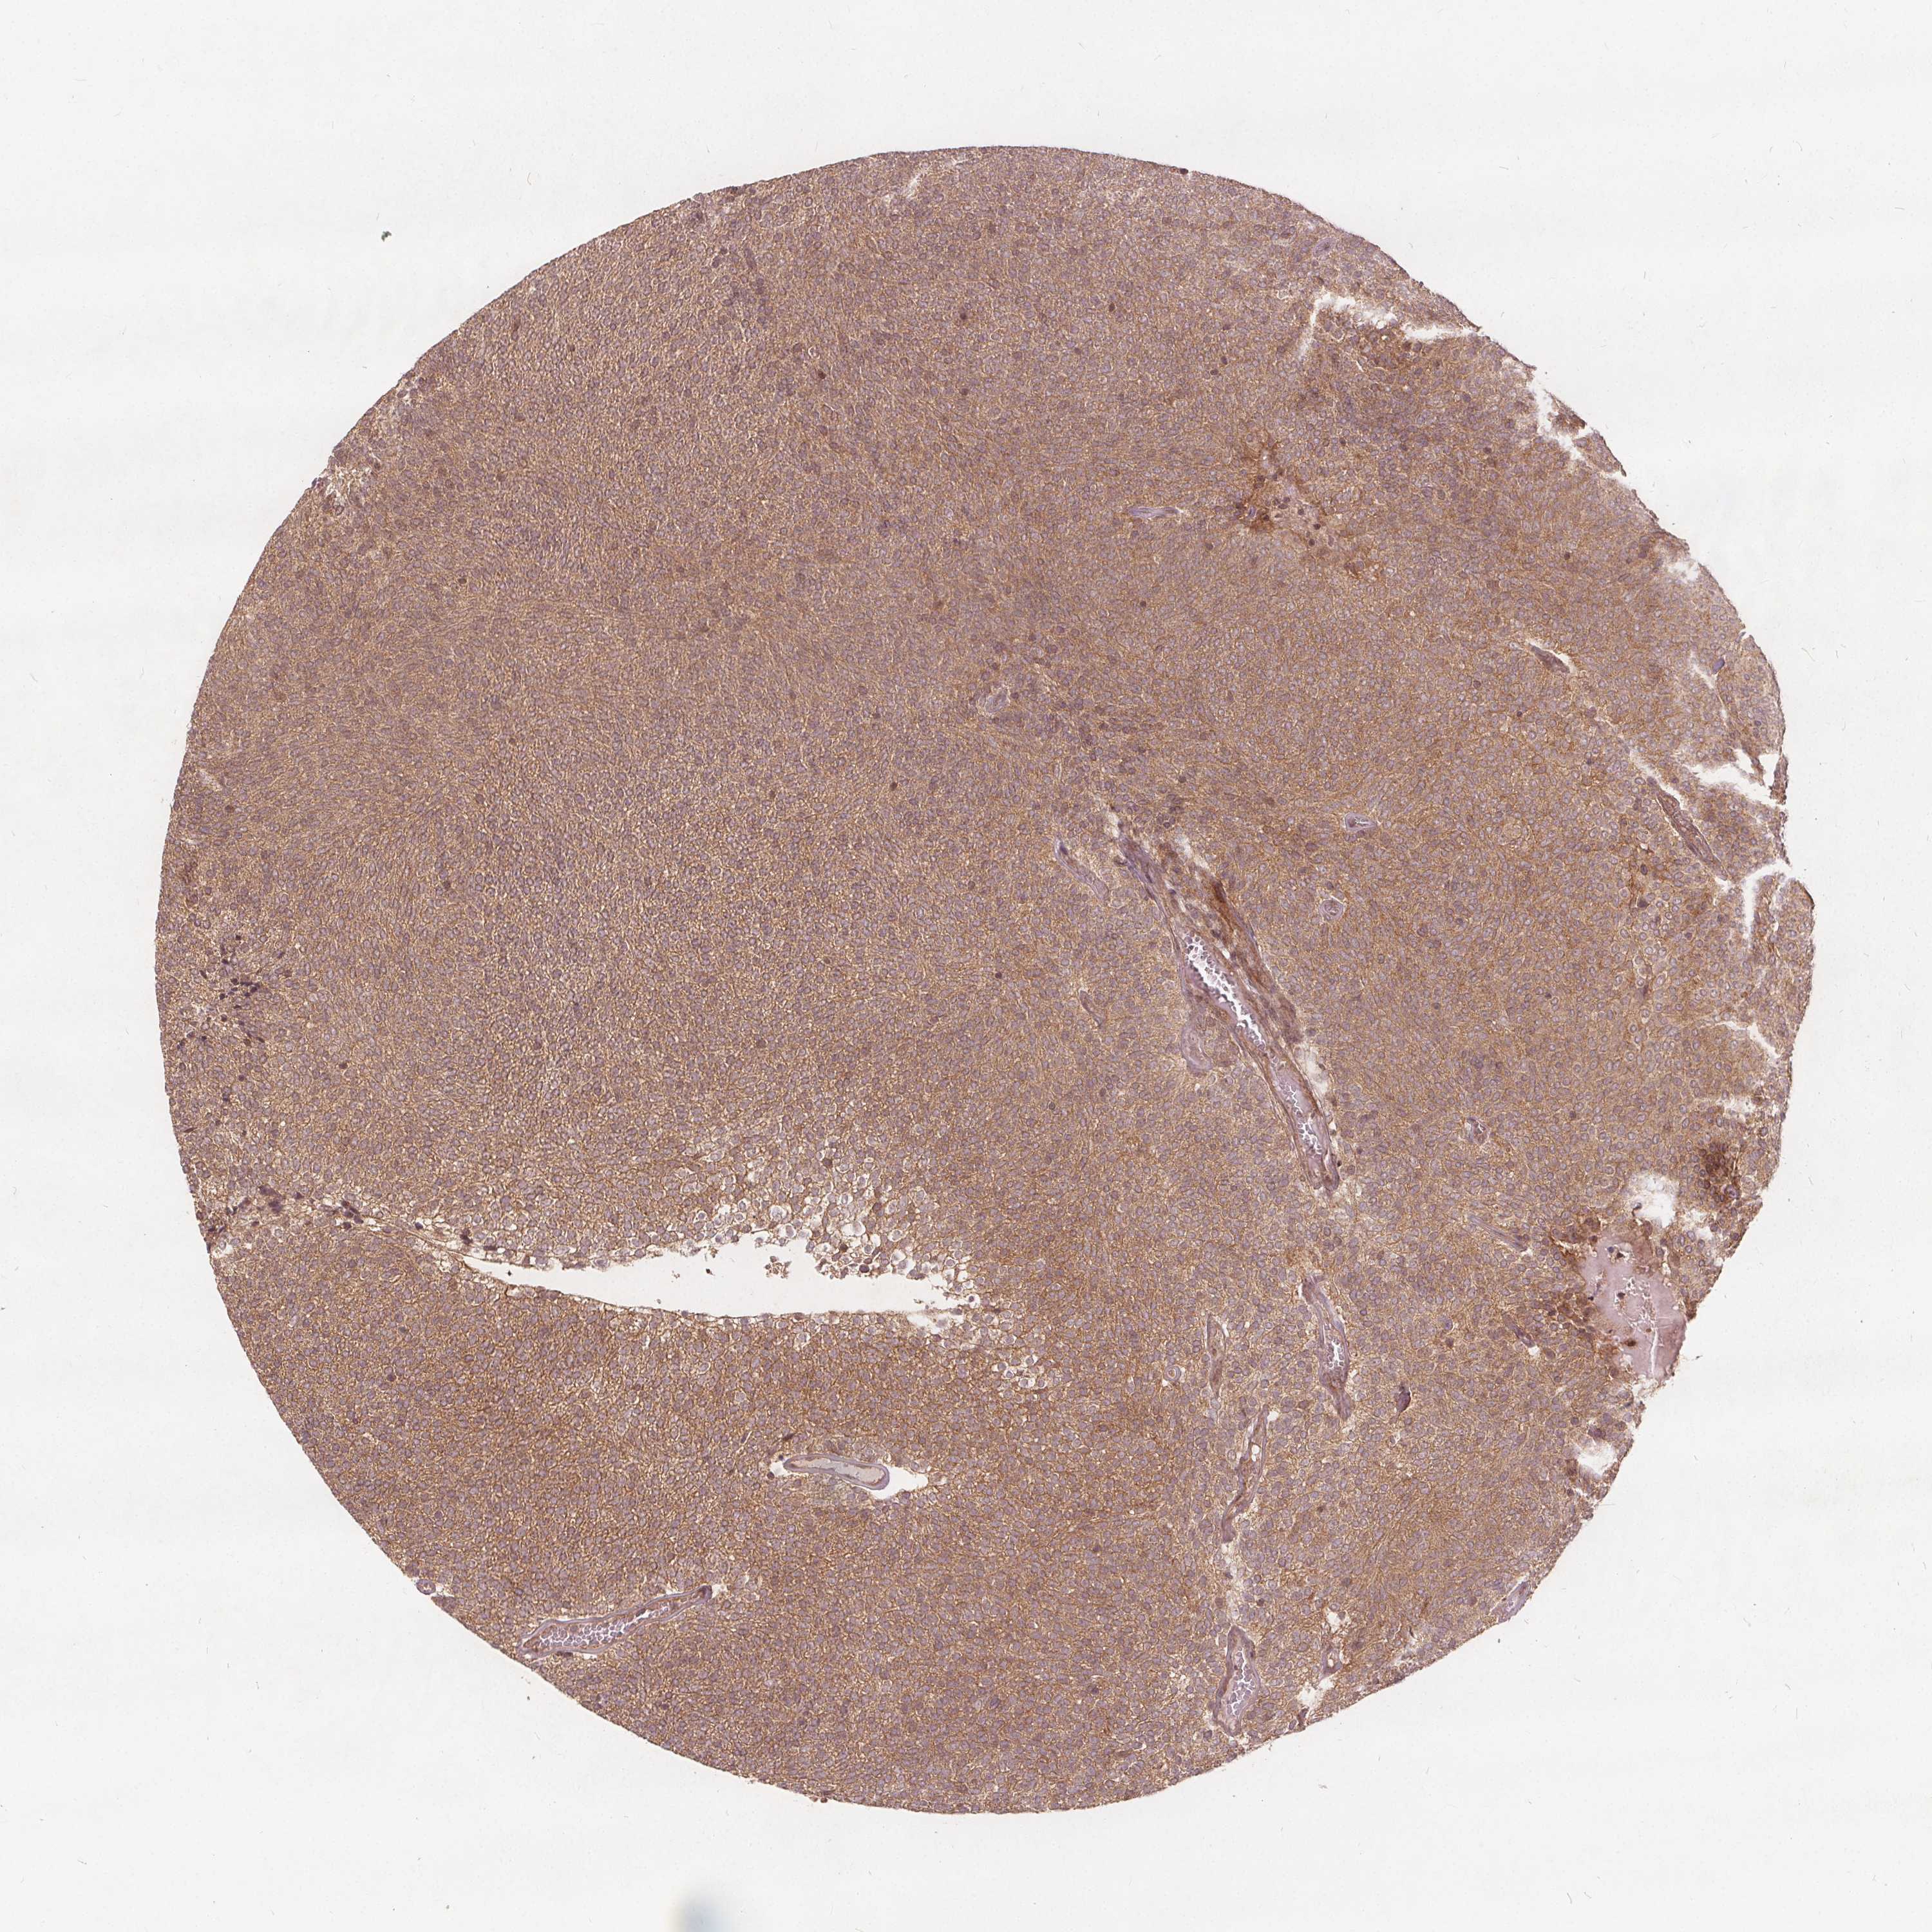

UROTHELIAL CANCER - Protein expressioni

A mouse-over function shows sample information and annotation data. Click on an image to view it in a full screen mode. Samples can be filtered based on level of antibody staining by selecting one or several of the following categories: high, medium, low and not detected. The assay and annotation is described here.

Note that samples used for immunohistochemistry by the Human Protein Atlas do not correspond to samples in the TCGA dataset.

Antibody stainingi

Antibody staining in the annotated cell types in the current human tissue is reported as not detected, low, medium, or high, based on conventional immunohistochemistry profiling in selected tissues. This score is based on the combination of the staining intensity and fraction of stained cells.

Each image is clickable and will lead to virtual microscopy that enables deeper exploration of all samples and also displays staining intensity scores, fraction scores and subcellular localization as well as patient and tissue information for each sample.

Antibody HPA065425

Antibody CAB069426

Urothelial carcinoma, High grade

Urothelial carcinoma, NOS

Urothelial carcinoma, Low grade